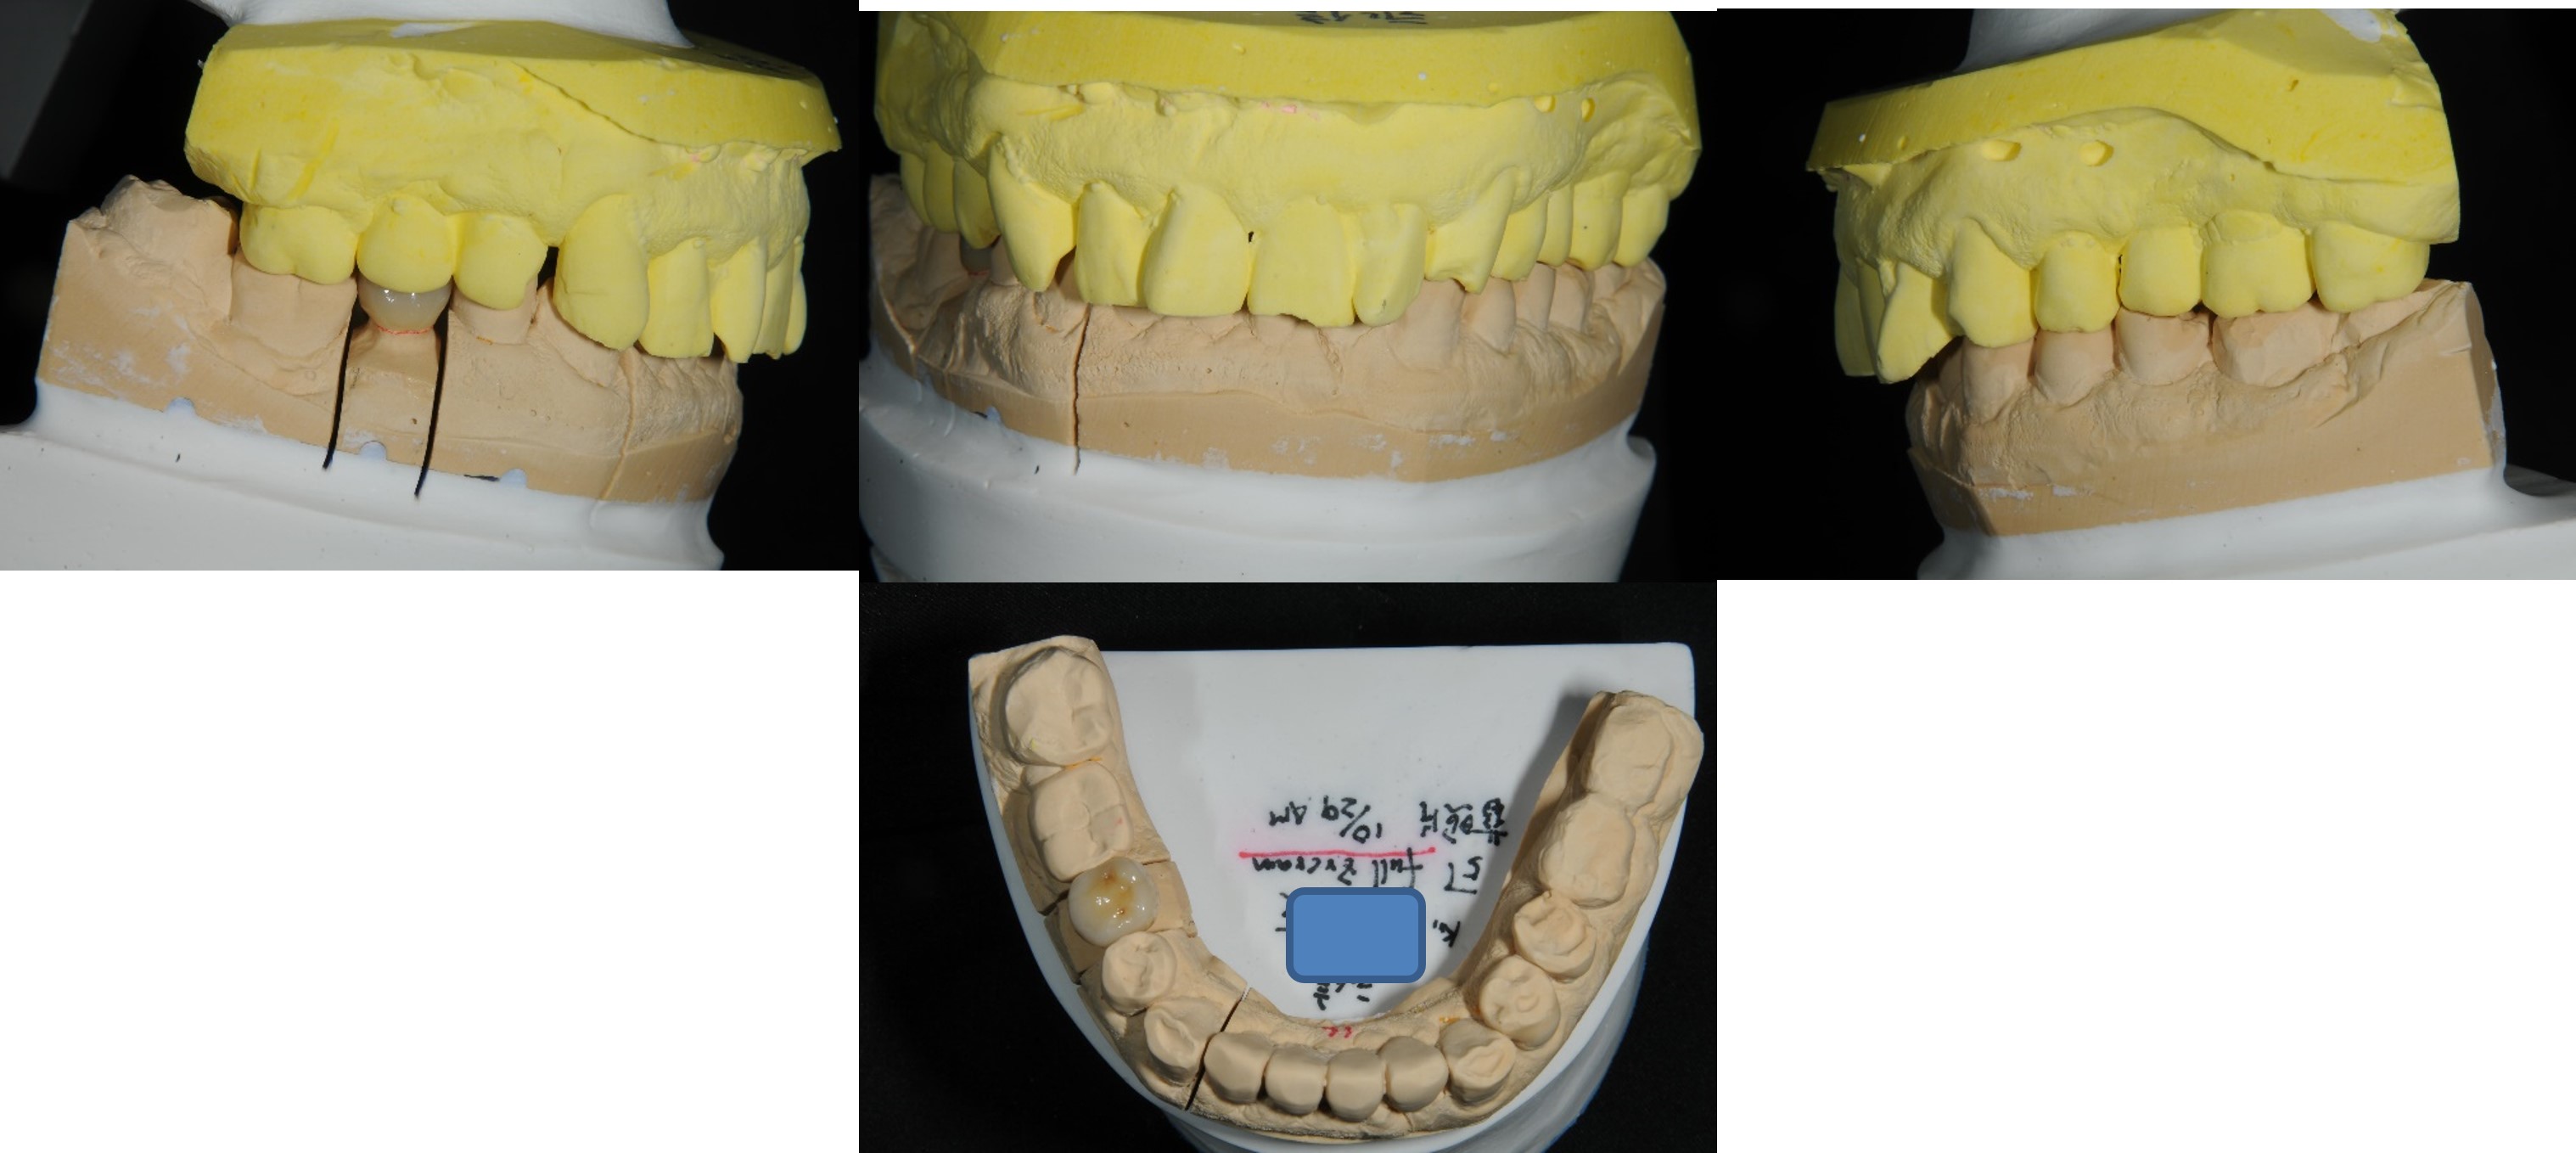

半調節咬合器上製作膺復物

咬合器上製作製作固定膺復物